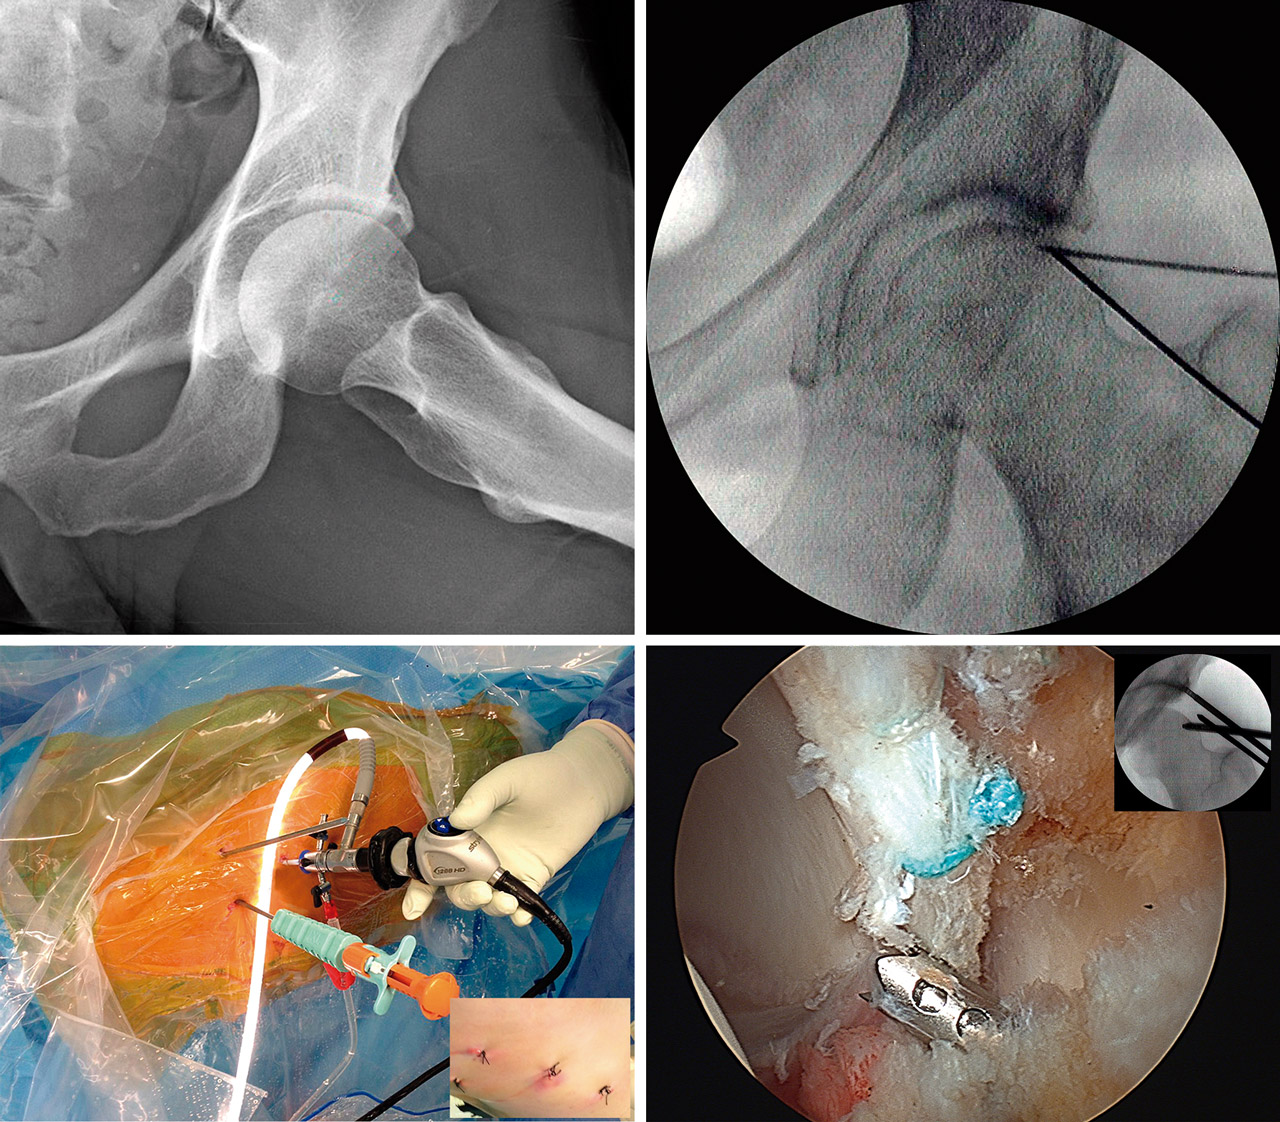

El abordaje artroscópico de las formas de tipo PINCER y otros procesos del reborde acetabular

The arthroscopic approach of the PINCER-type forms and other processes of the acetabular rim